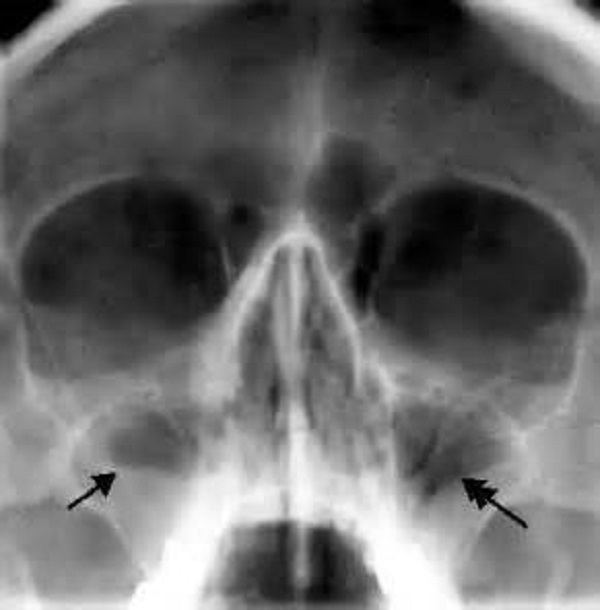

Верхняя челюсть содержит придаточные пазухи, такие как гайморовые, которые расположены над верхней челюстью, а также в лобных костях и костных клетках решетчатой и внутри клиновидной кости, которые играют роль в формировании основы черепа. У новорожденных внутри гайморовой пазухи находятся зачатки зубов, и полость в этой области появляется только после того, как эти зубы начинают расти.

Однако при воспалительных заболеваниях в носовой полости слизистая может увеличиваться в объеме, что препятствует нормальному оттоку из пазух, и способствует быстрому размножению микроорганизмов, вызывающих воспаление. Для лечения этого состояния врачи активно применяют антибактериальные препараты, уничтожающие патогенные микробы.